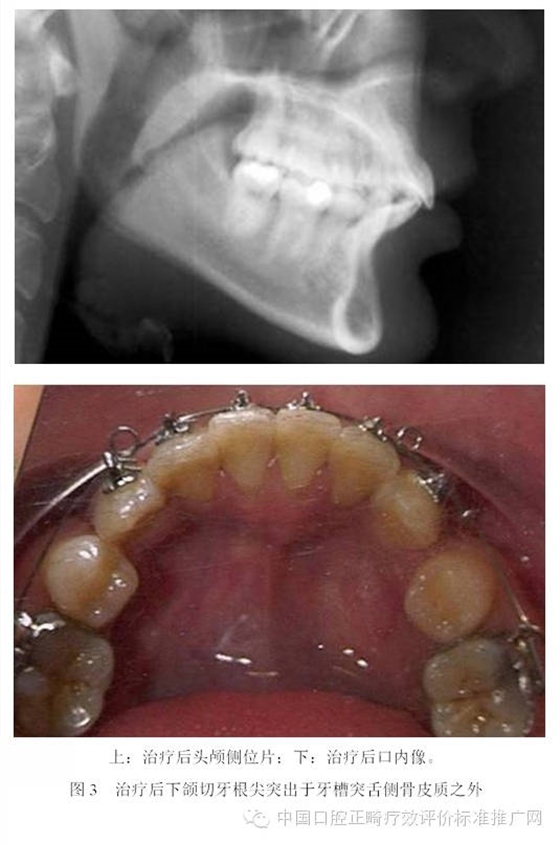

為了避免支抗的丟失,正畸醫(yī)師終于發(fā)現(xiàn)了最強(qiáng)的支抗裝置---金屬種植釘支抗。在用支抗磨牙拉前突的切牙時,切牙牙根在接觸腭側(cè)骨皮質(zhì)后移動的阻力會非常大,于是支抗磨牙會前移而最終關(guān)閉間隙;但當(dāng)改用種植釘支抗拉前牙時,由于種植釘是絕對支抗,在矯治力作用下幾乎不動[6],因此當(dāng)切牙牙根與腭側(cè)骨皮質(zhì)接觸后,種植釘仍然不會作任何讓步,那么進(jìn)一步對抗的結(jié)果會怎么樣?理想的結(jié)果是腭側(cè)骨皮質(zhì)的牙根一側(cè)發(fā)生骨吸收,而舌側(cè)骨板發(fā)生骨沉積,牙齒帶著牙槽骨一起向腭側(cè)移動。問題是骨吸收與骨沉積的數(shù)量相等嗎?速度一致嗎?為了回答這個問題,筆者[7]10年前作過一個上頜切牙內(nèi)收對其前后方牙槽骨改建的探索性研究。該研究選擇55例平均年齡為13.3歲的青少年錯合患者為研究對象,采用拔除上下頜第一前磨牙進(jìn)行矯治,平均保持時間為3年。通過測量上切牙阻力中心前方及后方牙槽骨在治療前、治療后及保持后的骨量變化,以及牙槽突總厚度在上述3個時間點的變化,結(jié)果發(fā)現(xiàn):上切牙阻力中心在治療后向腭側(cè)平均移動了1.8mm (P<0.001);與阻力中心水平的唇側(cè)牙槽骨厚度增加了0.2mm (P<0.01),腭側(cè)牙槽骨厚度減小了0.8mm (P<0.001);隨訪期上切牙阻力中心向唇向復(fù)發(fā)了0.8mm (P<0.01),與阻力中心水平的唇側(cè)牙槽骨厚度相應(yīng)減小了0.2mm (P<0.05),但腭側(cè)牙槽骨厚度卻并沒有明顯的增加;與上切牙阻力中心水平的牙槽突總厚度基本保持在治療后的水平。由此可見,在牙齒移動的過程中,牙槽骨的生物學(xué)改建是以骨吸收為主,骨增生十分有限,即使是保持3年以后,骨增生的量也未達(dá)到其吸收的量。雖然這只是個初淺的臨床研究,尚有待基礎(chǔ)研究去證實,但它卻部分解釋了正畸臨床上在對骨性錯合患者進(jìn)行牙代償性矯治時,會出現(xiàn)牙槽骨吸收、裂隙、穿孔,牙齦萎縮或部分根尖移出牙槽骨的現(xiàn)象[8-13]。圖3為1例成人患者在用牙代償性治療方法減少重度深覆蓋深覆合時出現(xiàn)切牙根尖從舌側(cè)移出牙槽骨的X線影像;圖4為1例采用種植釘支抗大量內(nèi)收上下頜前牙的患者,治療后牙根移出至牙槽突之外的錐形束CT影像。